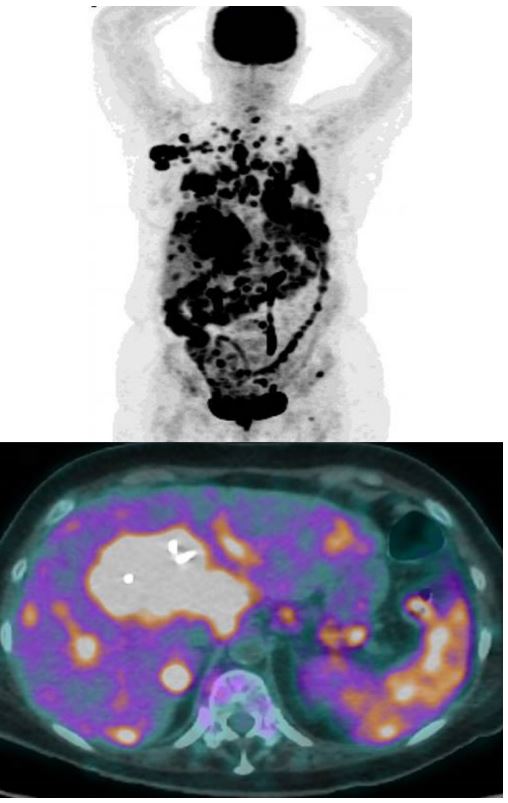

Computed tomography of the chest and abdomen disclosed pathological contrast and wall thickening of the proximal bile duct and right hepatic duct. The left hepatic duct was no longer visible due to diffuse tumor infiltration of the central hepatic parenchyma resulting in dilatation of the intrahepatic bile ducts. A complete occlusion of the biliary convergence with complete separation of the bile ducts to the 2nd convergence was observed. In addition, multiple adenopathy of the hepatic hilum, celiac, gastric greater curvature and retroperitoneal and cardio-phrenic were visible (Figure 1). Magnetic resonance imaging confirmed the CT findings with additional intrahepatic, vertebral body metastases and multiple pulmonary nodules (Figure 2).

Figure 1: Thoraco-Abdominal CT scan.